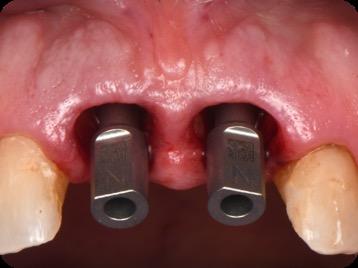

BioHorizons has introduced a new implant system that combines the advanced thread design of the Tapered Pro with the precision and stability of the Conelog conical connection. This integration delivers enhanced surgical handling, improved primary stability, and long-term biological benefits, supporting better patient outcomes in both aesthetic and functional zones.

This case was performed by Dr Homa Zadeh, DDS, PhD, a respected leader in periodontology and implant dentistry. Dr Zadeh’s approach emphasizes biologically driven protocols and evidence-based techniques, making this case a strong example of clinical excellence using the Tapered Pro Conical system. It involves the replacement of two front anterior teeth after they fractured off and the full restoration process.

Fig 8. Scanbody installation for custom abutment and definite restoration fabrication.

Fig 9. Periapical radiograph for verification of proper seating of the scanbodies.